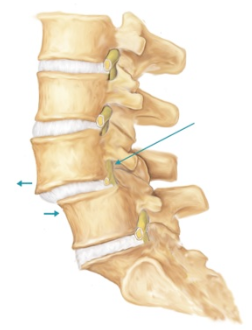

Le spondylolisthésis est le glissement vers l’avant d’un ensemble de vertèbre (segment rachidien) par rapport à la vertèbre suivante. Ce glissement peut théoriquement survenir à tous les étages vertébraux, mais concerne presque exclusivement le rachis lombaire. Les causes sont diverses : congénitales, dégénératives, ou traumatiques.

- compression des éléments nerveux (nerfs).

Ce test d’hyperlordose en décubitus ventral facile à mettre en œuvre avec des gymnastes petites et légères est plus difficile à envisager avec un rameur toute catégorie. Le diagnostic est donc essentiellement confirmé par des radiographies standard (face et profil debout, obliques de 3/4 droit et gauche). Cet examen est indispensable pour évaluer la statique du rachis, vérifier l’intégrité des vertèbres et classifier la lésion. Dans certains cas, des examens radiologiques dynamiques sont pratiqués (radiographies en flexion et extension). Le scanner peut apporter une meilleure définition de la qualité osseuse et montrer une éventuelle fracture associée (apophyses articulaires désolidarisées du corps vertébral).

Dans les cas les plus invalidants, l’IRM évalue l’état des disques intervertébraux, et permet de visualiser directement les nerfs et la qualité de la musculature para vertébrale.